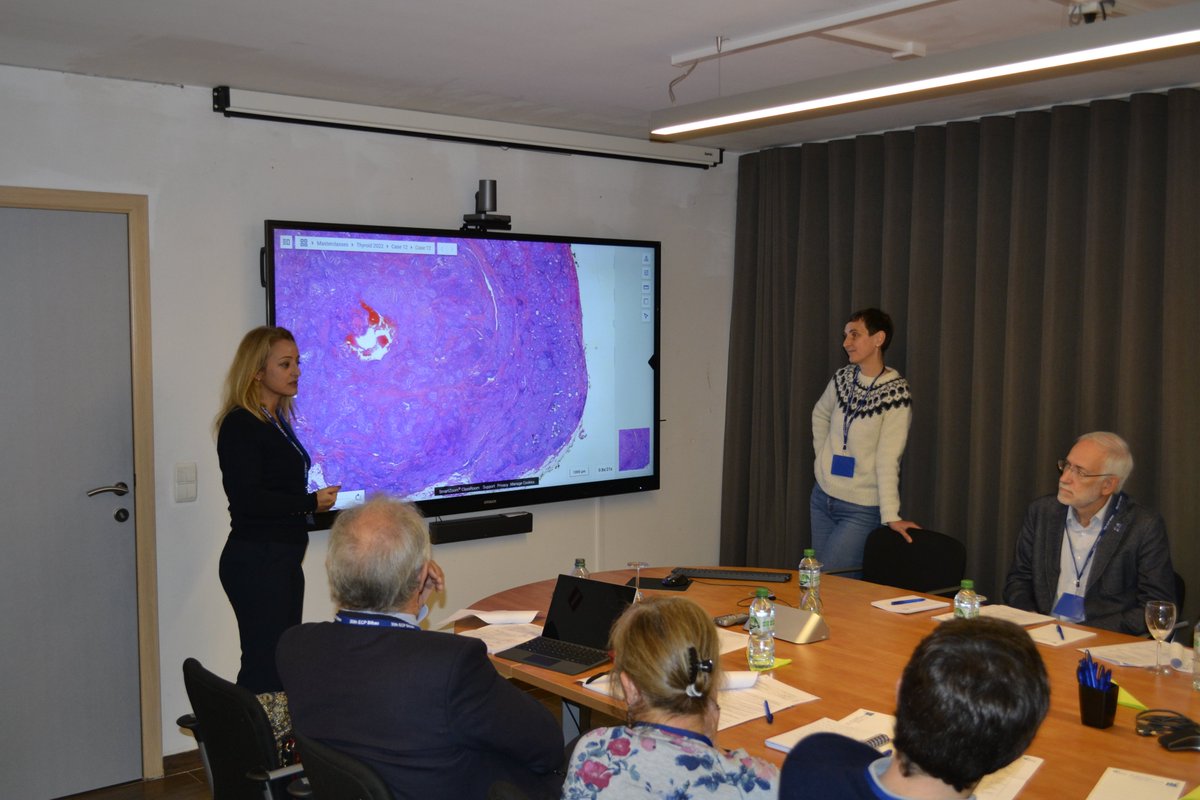

Very good conference in the European Society of Pathology (ESP) Meeting at #USCAP2023 by Catarina Eloy, MD,PhD It was pleasure see you again ☺️ Pic with Héctor-Enrique Torres-Rivas, MD an expert in Cytology and interventional cytology 💉

Today at #USCAP2023 the European Society of Pathology (ESP) companion meeting took place! We would like to thank the moderators, speakers and most of all the attendees for an exciting meeting with lively discussions! #PathTwitter